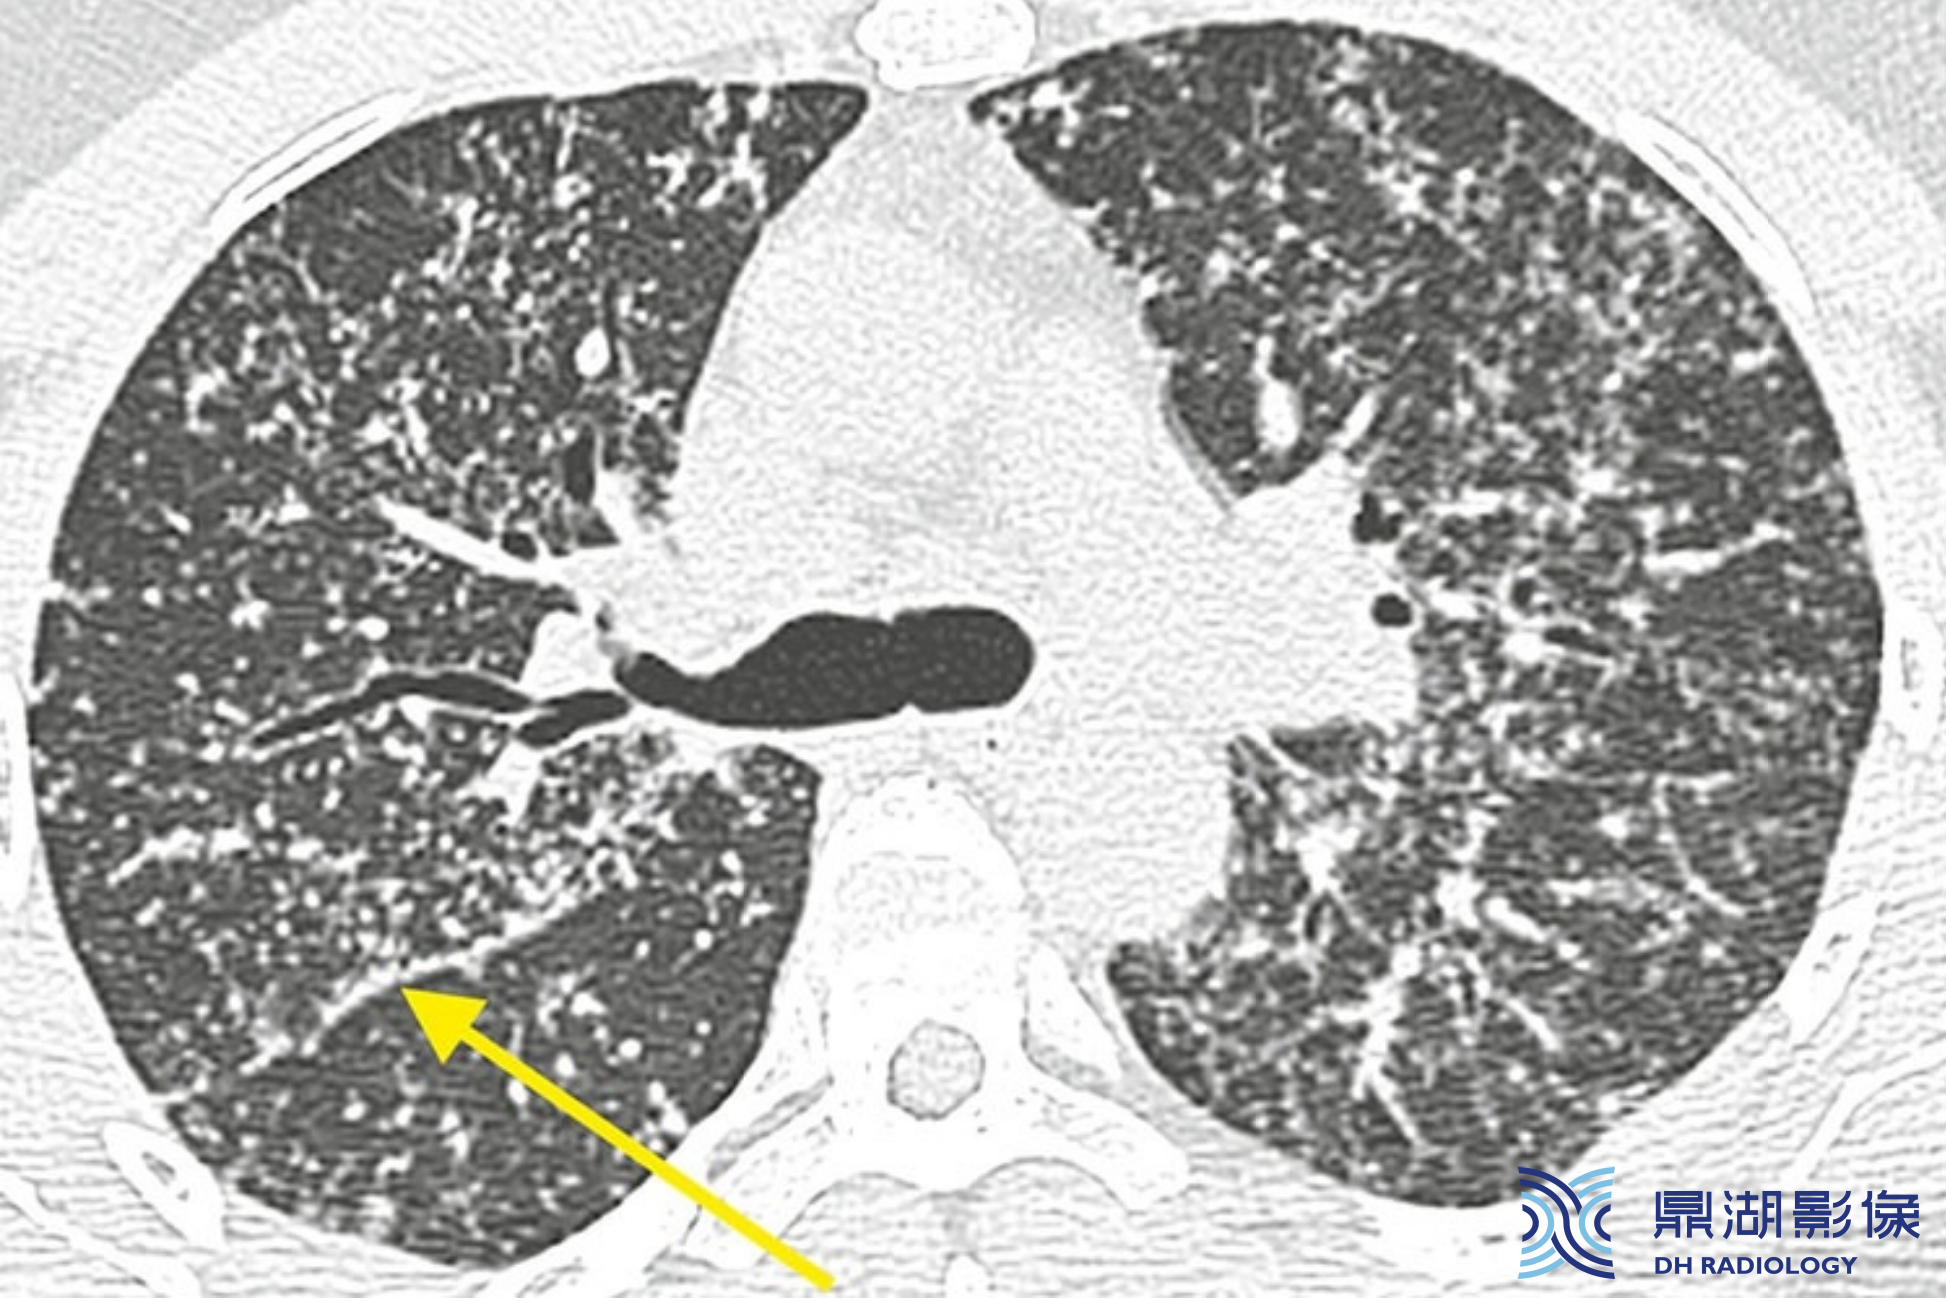

e7e783dec0c133d6d0659d8f8a9d13a1.png

结节病伴有类似随机分布的结节。粗略地看,结节呈随机分布且全肺受累。仔细观察可见结节呈散在不均匀分布,沿着叶间裂分布的结节(箭)数量多于随机分布的结节。

上述这种表现为淋巴分布结节加随机分布结节的模式,实际工作中更常见于肿瘤转移、癌性淋巴管炎,亚洲的结节病发病率要低于恶性肿瘤。